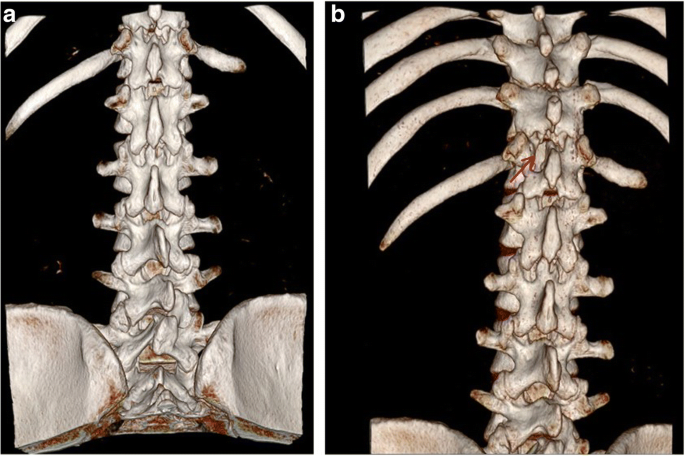

Spinal extradural arachnoid cysts are rare, and their origin and pathogenesis remain unknown. Some consider that an idiopathic spinal extradural arachnoid cyst is caused by herniation of arachnoid tissue through a congenital dural defect or invasion of a congenital dural diverticulum [1, 2]. Previous researches hypothesized that dural defects are like “one-way valves”, permitting CSF flow into the cyst under high CSF pressure from the subarachnoid space [3]. There are many surgical options including simple osseous decompression, incision and drainage, subtotal or total cyst resection, and marsupialization of the cyst [4]. Eroglu et al. reviewed 13 patients with spinal arachnoid cysts (SAC) who underwent surgical intervention. All performed fenestration of the cyst wall into the subarachnoid space at least including five total resection. There was recurrence in those patient during mean 55 months follow-up [5]. Fam et al. published 22 adults with spinal arachnoid cysts (SAC) in a single center including the six patients with extradural SAC and concluded that surgical exploration and complete resection is the treatment of choice [6]. Complete excision of the cyst followed by tight closure of the fistula by suture is suggested [1]. Total resection could be hard because the cyst might adhere tightly to the dura or the nerve tissue, or because of intraoperative bleeding from well-developed epidural venous plexuses. Intraoperatively letting a small part of the cyst wall remain should not increase recurrence since re-accumulation of fluid and recurrence of symptoms after the initial cyst removal are rare [7]. Complete cyst excision with fistula closure is the most successful surgical approach. If it cannot be achieved, either complete cyst excision without fistula closure or fistula closure with partial cyst excision can also achieve satisfactory surgical outcomes [8]. Several minimally invasive alternative surgical procedures have been reported such as selective laminectomy with fistula closure, shunts, and imaging-guided aspiration. Other techniques have been used in treating giant arachnoid cysts. Neo et al. proposed a case with extradural arachnoid cyst detected by a pulsating flow voiding observed at Cine-MRI and detected the location of the communication site of level L1 [9]. Nakagawa et al. presented a case with large extradural SAC and found the benefit at 3D constructive interference in steady state (CISS) MRI because of the additional surgery aimed at closing the dural defect [10]. Mishra et al. demonstrated intraoperative dynamic magnetic resonance myelogram for detecting the site of the fistula [11]. Gu et al. used digital subtraction cystography to detect a communicating hole between a cyst and the subarachnoid space [12], and Takamiya et al. injected pyoktanin blue into spinal arachnoid cysts to aid in total excision [13]. Endo et al. offered the less invasive surgical method of endoscopic fenestration to manage spinal intradural arachnoid cysts [14]. In this case, the giant extradural arachnoid cyst had multiple spinal segment involvement; therefore, a laminotomy or laminectomy might be performed at the multiple involving segments. The postoperative bony defect may induce structural instability and deformity, and spinal fusion and fixation should also be performed after cyst excision. Considering the young age and postoperative life quality of the patient, minimal invasive surgery was preferred and how to localize the fistula became the top priority. We proposed a preoperative method that utilizes real-time radiography under digital subtraction angiography and high resolution computed tomography. If this method accurately locates the fistula, ligation can be successful under minimally invasive laminotomy. In addition, the intraoperative use of the spinal endoscopic technique and a microscope enhances surgical safety, which decreases the damage of nerve roots and cords and other complications in the clear operative field. A postoperative follow-up 3-D reconstructive computed tomography revealed that only a small part of lamina was removed (Fig. 11). Such a small wound was one reason for the rapid postoperative recovery. A disadvantage for patients might be the radiation exposure. The follow-up period was short, so the recurrence may be adjusted in the future. This is one of our study limitations.